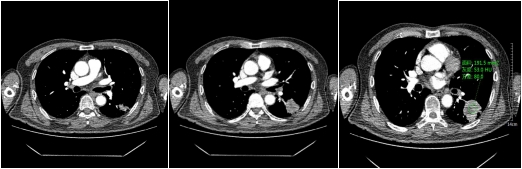

動脈期

靜脈期

以上肺結節(jié)影像表現(xiàn),只要出現(xiàn)其中一項或兩項,我們就要高度懷疑結節(jié)惡性,需要進一步CT增強檢查,排除結節(jié)的良惡性,更全面了解結節(jié)的性質。